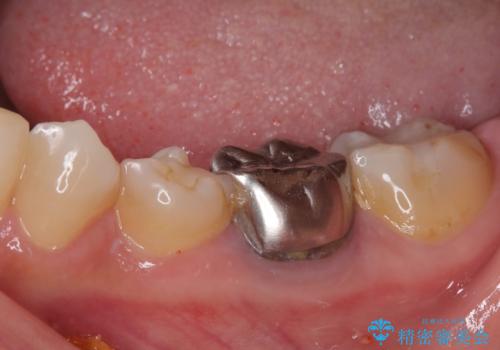

- 近医にて抜歯が必要と診断されたとのことで来院された患者様です。

術前の診査では、歯が破折している可能性が高いものの、確実に抜歯が必要と診断ができない状態でした。

状況次第では抜歯が必要となり、その際にはインプラント治療を行うことを了承いただいた上で、破折していない場合には根管治療を行うこととしました。

土台の材料を外して顕微鏡下で確認したところ、歯根にまで及ぶ破折が認められたため、インプラント治療を行うこととしました。